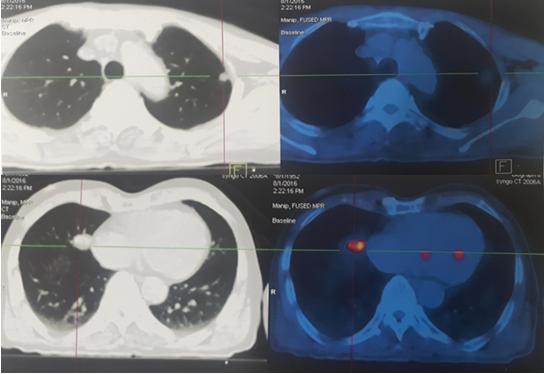

Hình 2: Hình ảnh tổn thương di căn phổi trên PET/CT

Nhiều nốt tổn thương hai phổi kích thước max: 3,7x4,1cm, tăng hấp thu FDG, maxSUV: 14,1